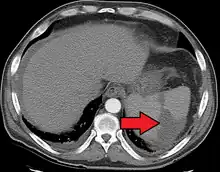

Splenic infarct seen on CT

Splenic infarction is a condition in which blood flow supply to the spleen is compromised,[1] leading to partial or complete infarction (tissue death due to oxygen shortage) in the organ.[2] Splenic infarction occurs when the splenic artery or one of its branches are occluded, for example by a blood clot.[3]

An abdominal CT scan is the most commonly used modality to confirm the diagnosis,[3] although abdominal ultrasound can also contribute.[5][6][7]